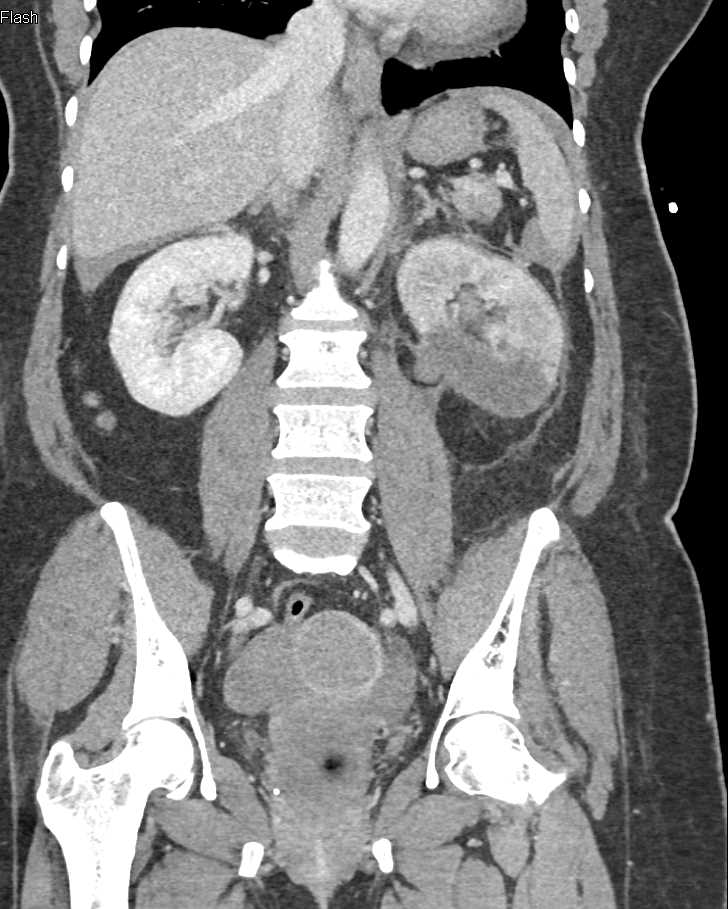

Acute Pyelonephritis Right Kidney